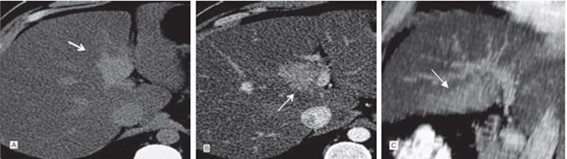

Es el tumor hepático benigno más frecuente. Histológicamente consiste en espacios vasculares delimitados por endotelio y separados por septos fibrosos. Contienen gran cantidad de sangre con un flujo muy lento. Pueden ser únicos (más frecuentes) o múltiples. Se observan como lesiones hipodensas, bien delimitadas en el estudio sin contraste. Tras la administración del medio de contraste pueden presentar tres tipos de reforzamiento dependiendo de su tamaño:

- Nodular, empezando desde la periferia de forma centrípeta; en fase tardía se verá como una lesión hiperdensa (lesiones medianas) (Anexo 18).

- Homogéneo inmediato en fase arterial (lesiones menores de 1 cm).

- Periférico centrípeto con persistencia de la zona central e hipodensa en fase tardía que corresponde a cicatriz o áreas de trombosis (lesiones de gran tamaño) (Anexo 19).(17-18)